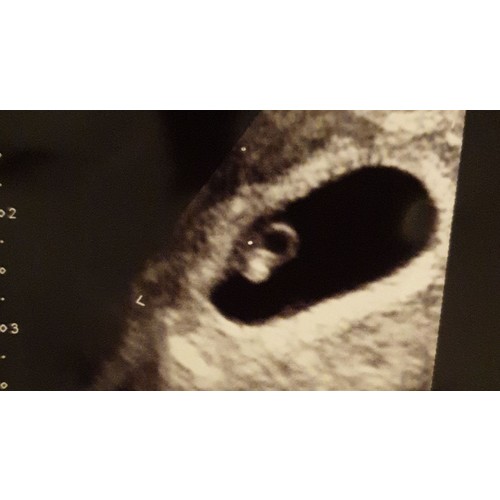

Dit was met bijna 7 weken

Heb zelf geprobeerd te ontdekken maar snap er w ...

Inwendig?

En is je profielfoto ook inwendig?